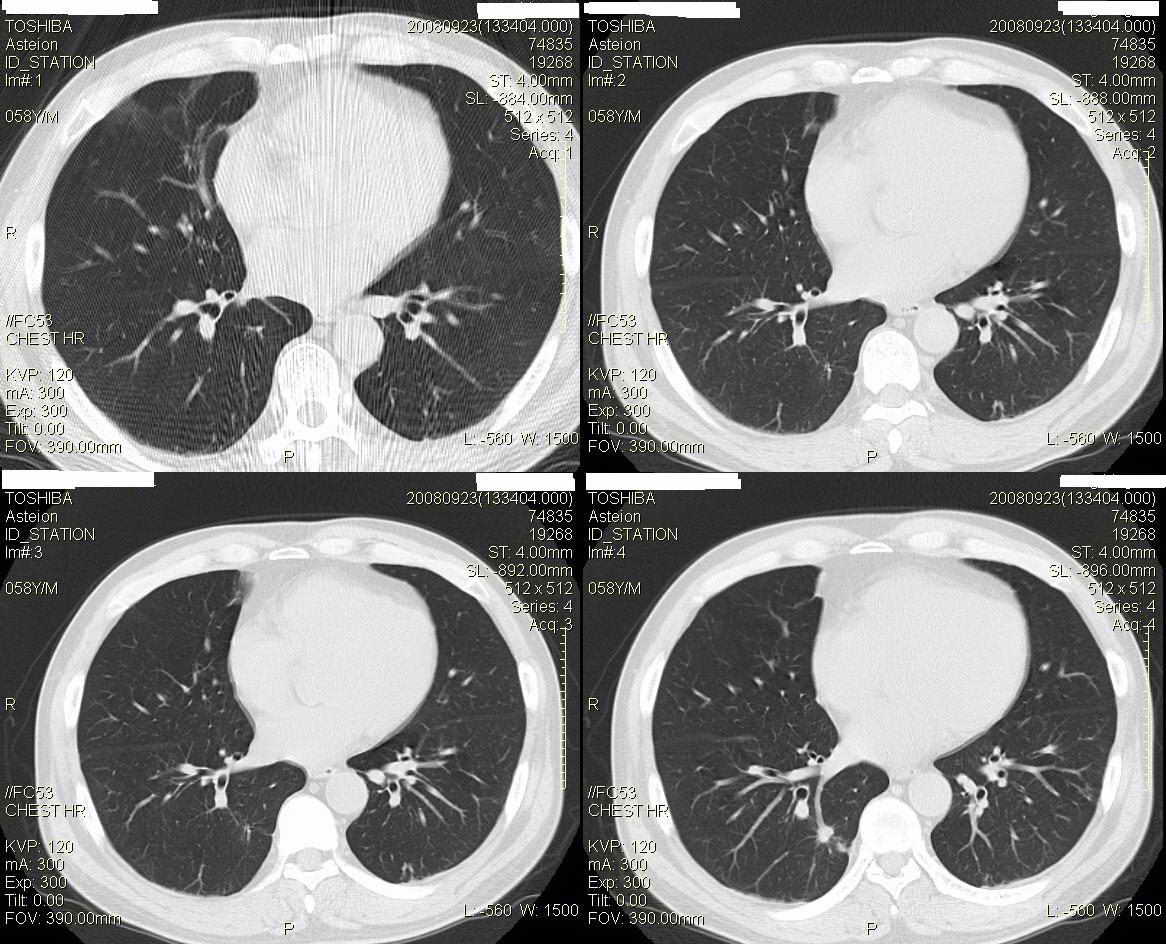

标题: CT15857:男性 58岁 咳痰带血 无发热 请各位大侠发表一下意见 [打印本页]

两肺下叶肺纹理增多、增粗并呈“树芽状”改变。支气管扩张呈囊状,部分呈柱状改变。其周围可见散在的斑片样及条索样密度增高影,右肺下叶近叶间胸膜可见一形态不规则的高密度结节影,并与胸膜粘连。

考虑:支扩并发感染。

双肺多发炎性病灶,结核可能性大,建议抗炎治疗复查.右肺下叶前基底段结节灶,高度警惕肺癌可能

双肺间质性改变(间质纤维化?)伴支扩。右肺下叶有毛刺的小结节,考虑周围型肺癌可能性。